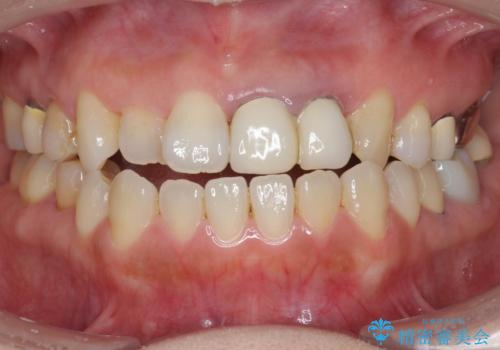

- 前歯がクラグラして噛めないことの改善を求めて来院されました。

X線撮影や歯周組織検査から、クラウン下の虫歯の再発や歯の破折が疑われる状況でした。

精度、周囲の歯の色調にこだわったオールセラミックブリッジを作製し、しっかりと機能・審美性を改善することができました。